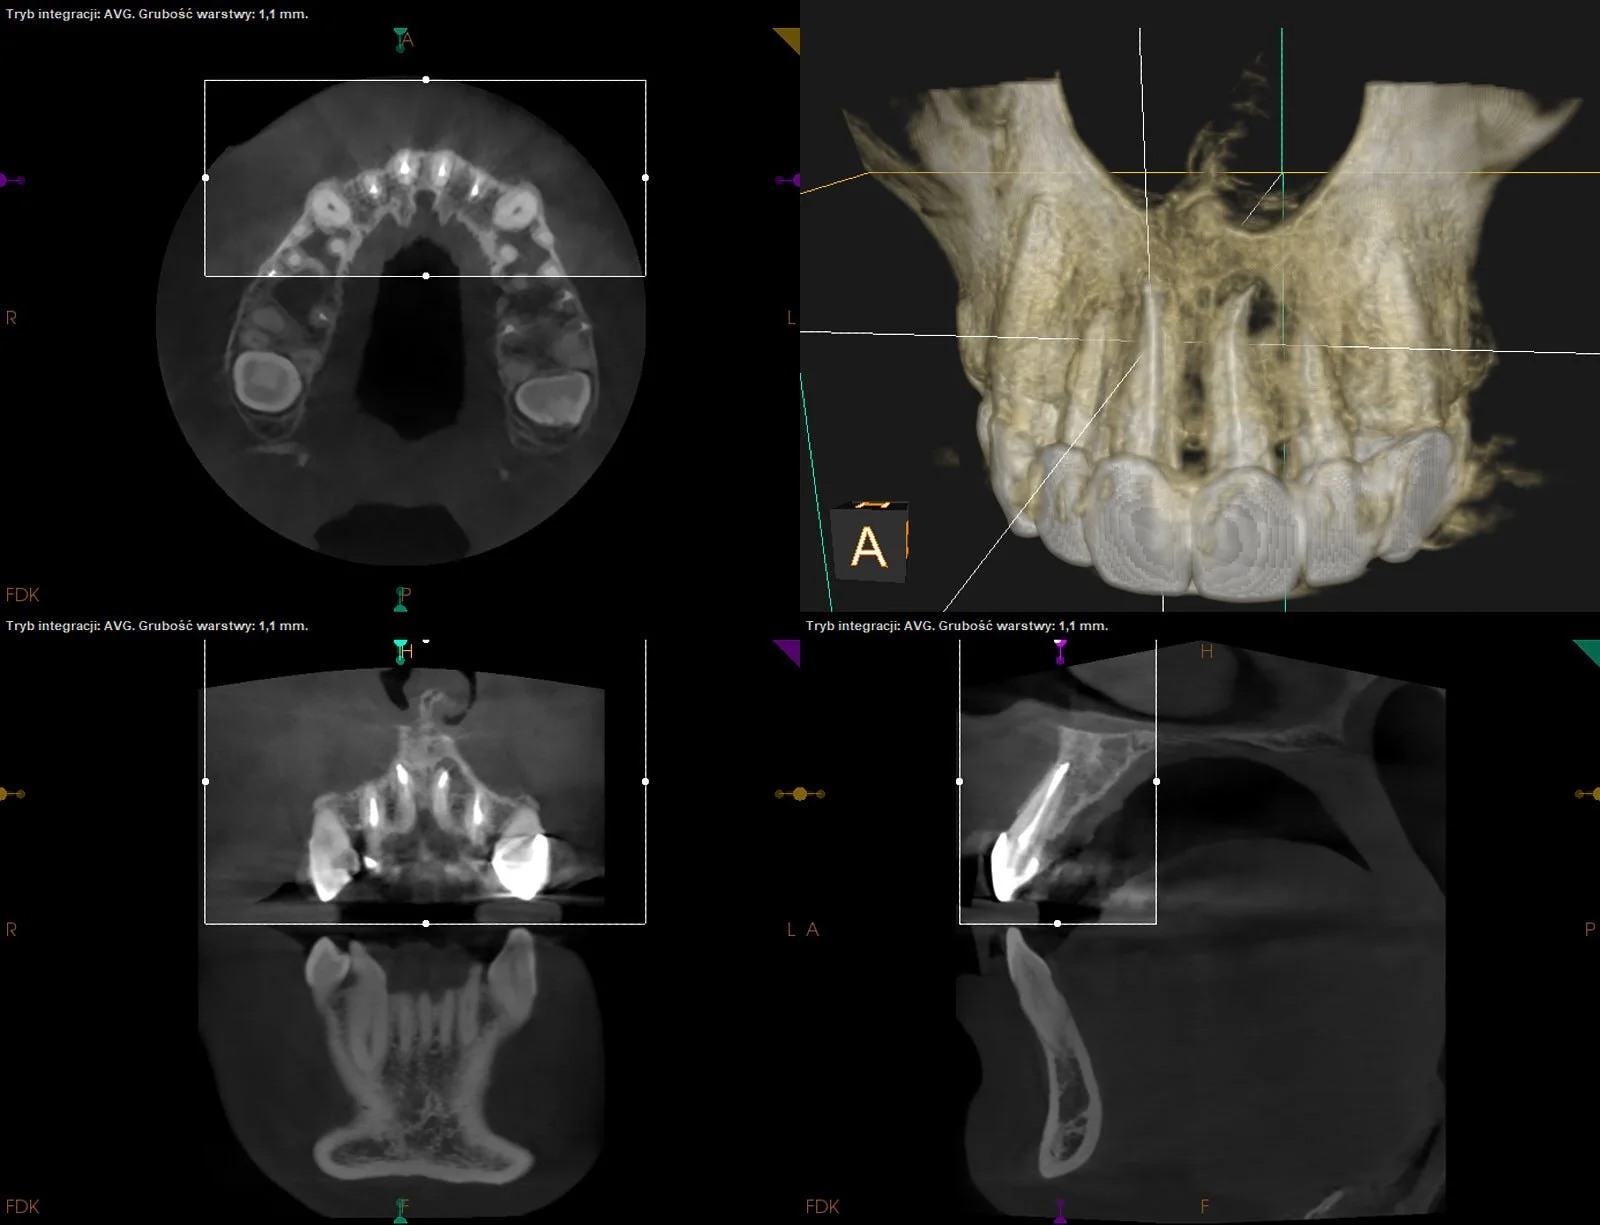

CASE STUDY II

CASE STUDY III

Leczenie kanałowe po dawnym leczeniu amputacyjnym wykonanym ponad 30 lat temu. Masywne obliteracje w przebiegu leczenia.

Pacjent w trakcie gojenia